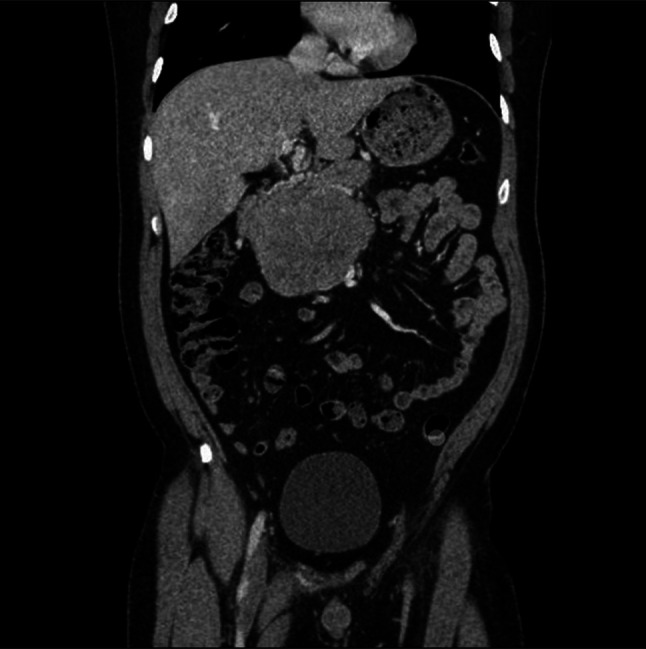

胰腺母细胞瘤(PB)是一种极其罕见的胰腺组织恶性肿瘤,占所有胰腺肿瘤的不到1%。由于罕见的恶性肿瘤和潜在的多种鉴别诊断,成人发病的PB可能是具有挑战性的诊断。诊断成人PB的主要特征是组织学。约90%的病例可见鳞状小体。我们提出一个病例的患者诊断为成人发病的PB,谁提出了关键的临床和病理特征,以及罕见的特征,与恶性肿瘤相关。

Pancreatoblastoma (PB), an extremely rare malignancy of the pancreatic tissue, comprises less than 1% of all pancreatic tumors. Owing to the rarity of the malignancy and the potential for multiple differential diagnoses, adult-onset PB can be challenging to diagnose. The hallmark characteristic in diagnosing adult PB is found histologically. In approximately 90% of cases, squamous corpuscles are observed. We present the case of a patient diagnosed with adult-onset PB, who presented with key clinical and pathological features, as well as rarer characteristics, associated with the malignancy.